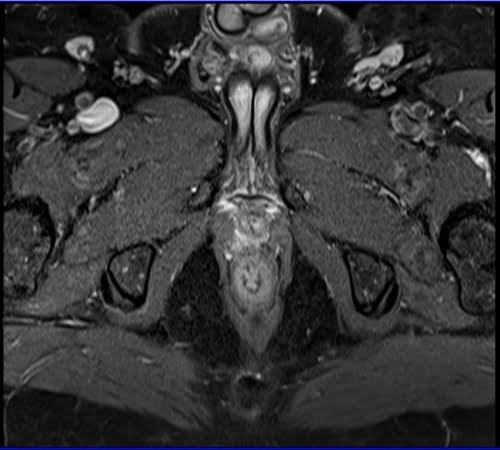

Prostatectomy patients prostate MRI T1 fat sat post contrast axial high resolution images